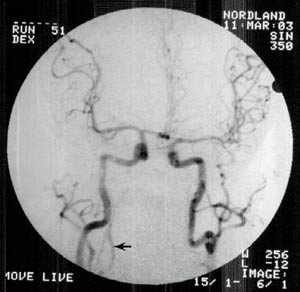

Det ble så, 24 timer etter hendelsen, utført arkografi som viste god sirkulasjon gjennom begge carotisarterier og i begge arteriae cerebri media og anterior (fig 2).

Vår antakelse om et globalt hjerneødem som årsak til Cushings refleks viste seg å være feil.

Ny cerebral CT ca. 25 timer etter hendelsen viste utbredt infarsering av hjernestamme, cerebellum og begge oksipitallapper samt begynnende hydrocephalus (fig 3). Gransking av arkografiundersøkelsen viste ingen fylling av venstre a. vertebralis og bare en meget langsom fylling av sentrale deler av en tynn høyre a. vertebralis. Det var ingen kontrastfylling av a. basilaris (fig 2).

Vi oppfattet nå tilstanden som en komplett basilarisokklusjon med ødeleggelse av hjernestamme, cerebellum og oksipitallapper, mens størstedelen av storhjernen hadde intakt sirkulasjon. Ved et sammenfall av en rekke uheldige omstendigheter forelå verken direkte observasjoner av hendelsen eller ambulanserapporten før arkografien ble utført 24 timer senere. Vi manglet altså nærmere opplysninger om pasientens anfall. Senere eksaminasjon av komparenter avdekket at pasienten antakelig ikke hadde hatt komplett respirasjons- eller sirkulasjonsstans på stedet der han falt om, og dermed var et globalt anoksisk ødem lite sannsynlig.